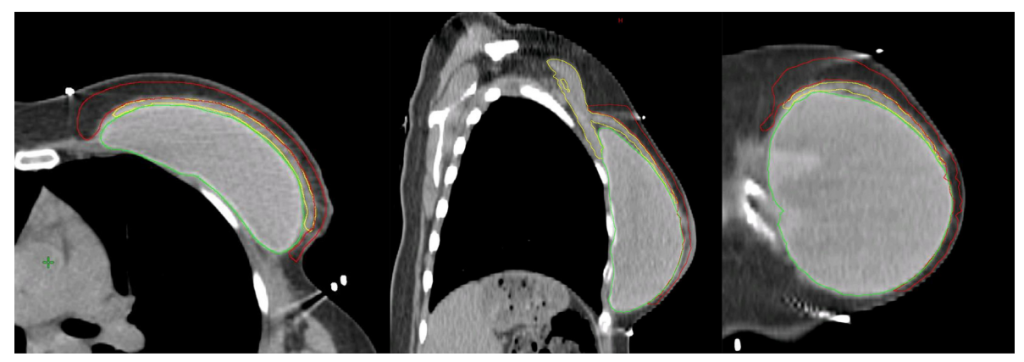

Hình 4b. CTVp_chestwall với phần trước (Đỏ) và sau (Xanh biển) trong trường hợp tổ chức bạch huyết dưới da cần được chiếu xạ cũng như phần thành ngực ban đầu không được bao phủ bởi cơ ngực lớn (Vàng). Túi độn sau cơ ngực (Xanh lá cây).

Nếu mạc sau tuyến vú không bị xâm lấn bởi ung thư, CTVp_chestwall cho PMRT không bao gồm mạng lưới bạch huyết sâu, do đó, chỉ bao gồm viền tổ chức mô phía trước cơ ngực lớn và túi độn, ngoại trừ ở phía trong, ngoài và dưới, nơi CTV có thể được mở rộng để bao phủ phần thành ngực không được bao phủ bởi cơ ngực lớn trước mổ. Như vậy, phần lớn túi độn có thể được loại khỏi CTVp_chestwall, trong khi các phần thành ngực xung quanh cơ ngực với các dòng chảy bạch huyết vẫn nên được bao phủ. (Hình 4a, b). Lớp cơ ngực phía trên túi độn có thể rất mỏng ở một số người bệnh, vì vậy, thể tích bia lâm sàng thường khó tránh khỏi phải bao gồm ít nhất một phần cơ ngực, nghĩa là giới hạn sau của CTV sẽ là bình diện trước của túi độn.

Với các bệnh nhân có yếu tố bất lợi và/hoặc nếu khối u nằm trong phần nhu mô tuyến sát mạc sau (Diện cắt tiệm cận, u nhuộm màu mực ở mạc sau tuyến vú) không được bao phủ bởi cơ ngực lớn (chủ yếu gặp ở các khối u phần thấp, thường nằm kết cận các xương sườn và cơ liên sườn), chỉ ngăn cách bởi mạc sau tuyến vú, chúng tôi khuyến cáo xác định thêm vùng tổ chức mô giữa thành ngực và túi độn ở phần thấp tính từ vị trí của cơ ngực lớn trước mổ (Lý tưởng nếu được đánh dấu bằng clip trong mổ), như một CTV phía sau tách biệt. (Hình 4B)